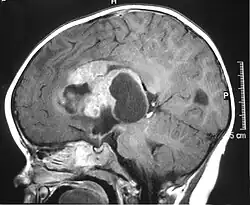

MRI of an AT/RT

The initial diagnosis of a tumor is made with a radiographic study (MRI[28] or CT-). If CT was performed first, an MRI is usually performed as the images are often more detailed and may reveal previously undetected metastatic tumors in other locations of the brain. In addition, an MRI of the spine is usually performed. The AT/RT tumor often spreads to the spine. AT/RT is difficult to diagnose only from radiographic study; usually, a pathologist must perform a cytological or genetic analysis.

Appearance on radiologic exam

AT/RTs can occur at any sites within the CNS; however, about 60% are located in the posterior fossa or cerebellar area. The ASCO study showed 52% posterior fossa; 39% sPNET; 5% pineal; 2% spinal, and 2% multifocal.[3]

The tumors' appearance on CT and MRI are not specific, tending towards large size, calcifications, necrosis (tissue death), and hemorrhage (bleeding). Radiological studies alone cannot identify AT/RT; a pathologist almost always has to evaluate a brain tissue sample.

The increased cellularity of the tumor may make the appearance on an uncontrasted CT to have increased attenuation. Solid parts of the tumor often enhance with contrast MRI finding on T1 and T2 weighted images are variable. Precontrast T2 weighted images may show an isosignal or slightly hypersignal. Solid components of the tumor may enhance with contrast, but not always. MRI studies appear to be more able to pick up metastatic foci in other intracranial locations, as well as intraspinal locations.